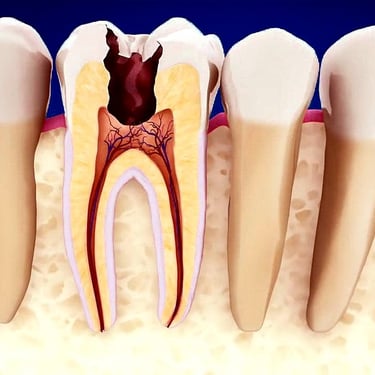

Pulpitis Irreversible

La pulpitis irreversible es una inflamación severa de la pulpa dental que no se puede curar por sí sola, a menudo debido a una caries profunda o una lesión grave.

Los pacientes suelen sentir dolor intenso y prolongado, especialmente con estímulos calientes.

La única solución es el tratamiento de conducto para salvar el diente. Sin tratamiento, la pulpa morirá y puede llevar a una infección.